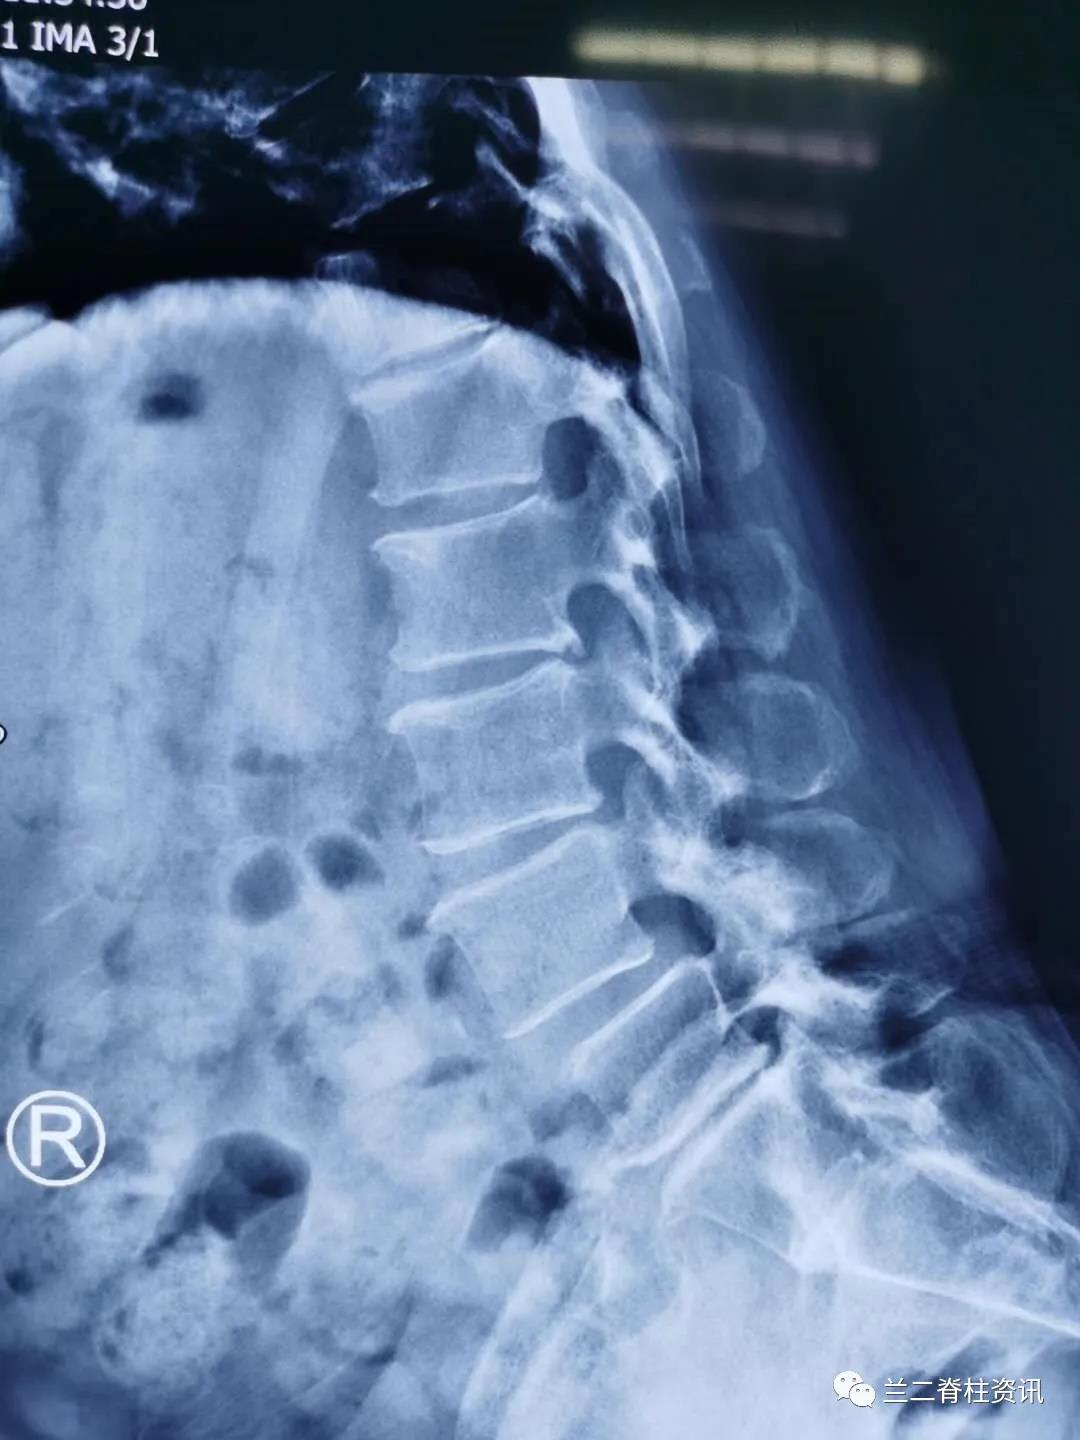

患者,女性,65岁,因“腰痛伴双下肢疼痛麻木三年”入院。入院后,骨科团队详细询问患者病史,在全面的病情评估和术前讨论后,制定详细周密的手术计划,并与患者及其家属进行充分沟通后,于近日成功实施单一体位OLIF融合术。术后第三天,患者感慨:“早知道手术不仅微创还效果这么好,就应该早点做手术,被病痛折磨的太久了”。

OLIF是近些年在前路和侧方入路手术技术的基础上,尤其是为了减少侧方经腰大肌手术入路带来的神经功能障碍问题发展和演变而来的新技术。从腹部切口,进入腹膜后,利用腰大肌和腹膜后血管鞘之间的自然间隙入路,处理椎间盘,并置入融合器,实现腰椎间盘突出、腰椎管狭窄、腰椎滑脱、原手术后临近节段退行性病变,甚至脊柱侧后凸畸形矫形等的治疗。

通常OLIF手术需用侧卧位微创植入融合器后变换体位(俯卧位)植入经皮椎弓根钉,该患者采用单一体位OLIF 融合术 ,利用c臂“徒手”植入经皮椎弓根螺钉。该技术允许在单一体位下“毕其功于一役”,简化了手术流程,缩短了手术时间,减少感染风险,降低变换体位导致的麻醉脱管等并发症,促进了术后康复,大大缩短了手术时间,真正实现了“高效、可视、精准、安全”的脊柱微创治疗理念。本例手术的成果,也标志着我院骨科在脊柱微创领域方面走在了国内前沿。